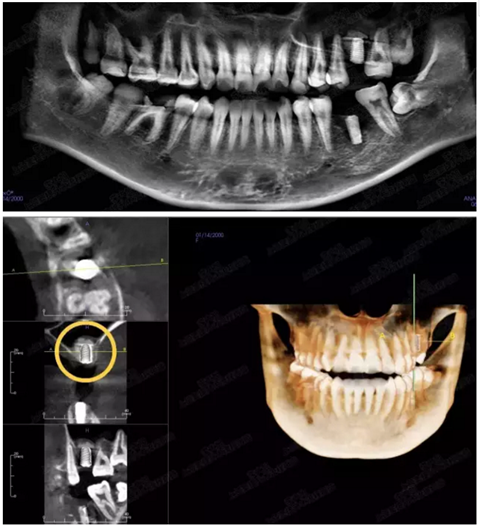

病例一

上頜竇多分隔3mm

05.png

提升8mm

06.png

07.png

修復(fù)時(shí)根尖片

08.png

09.png